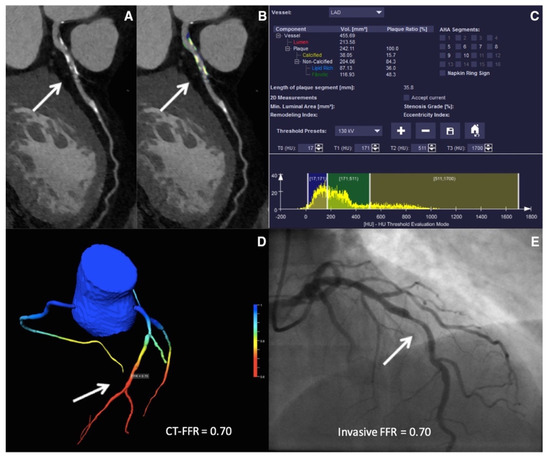

Figure 2.

ML-based fractional flow reserve from cardiac CT (CT-FFRML). Machine-learning-based coronary plaque analysis quantifies atherosclerotic plaque into calcified and noncalcified components (A,B). This is further integrated with other quantitative parameters (C) and transformed into 3-D images of the vessels to give CT-FFRML (D), which has been shown to have a good correlation with invasive fractional flow reserve (FFR—E). Adapted with permission from Von Knebel Doeberitz et al. [65], Elsevier.

Based on the concept of artery lumen segmentation, the ML-based FFR estimation (CT-FFRML) has generated significant interest in the past few years. The CT-FFRML model was trained on 12,000 synthetically generated coronary geometric datasets and used deep neural networks, allowing for automatic computation of FFR in real-time [93]. Coenen et al. performed a multicenter, prospective study to evaluate the diagnostic performance of CT-FFRML to predict lesion-specific ischemia, comparing it with traditional CCTA parameters, with invasive FFR being the gold standard [97]. They demonstrated an excellent correlation between CT-FFRML and FFRCT (r = 0.997) and a superior performance of CT-FFRML over traditional CCTA in predicting lesion-specific ischemia (AUC: 0.84 vs. 0.69, p < 0.001 on a per-vessel level). Since then, multiple retrospective studies have been performed to evaluate the diagnostic accuracy of CT-FFRML, validated against the gold-standard invasive FFR. They have further demonstrated superior diagnostic performance of CT-FFRML over CTA stenosis severity and quantitative atherosclerotic plaque features derived from CCTA [70,93,97,98,99,100,101,102,103,104,105,106,107].